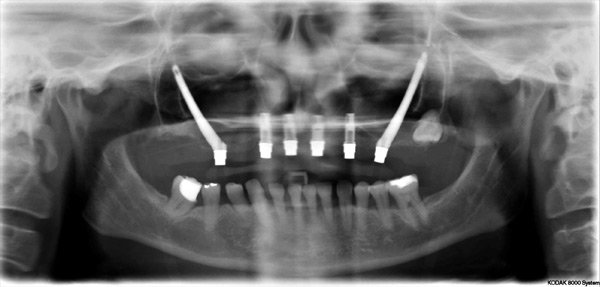

Problem: This patient comes in with badly broken-down teeth and periodontal disease. Her midline is off center. She wants something that will be anchored in so she can eat well and look fabulous.

Plan: Our plan… we removed the remaining teeth and placed four implants on the lower for a fixed/hybrid prosthesis. The upper required bone grafting and then placed eight implants that will support a connector bar prosthesis.

She is happy. We’re happy. Mission accomplished!